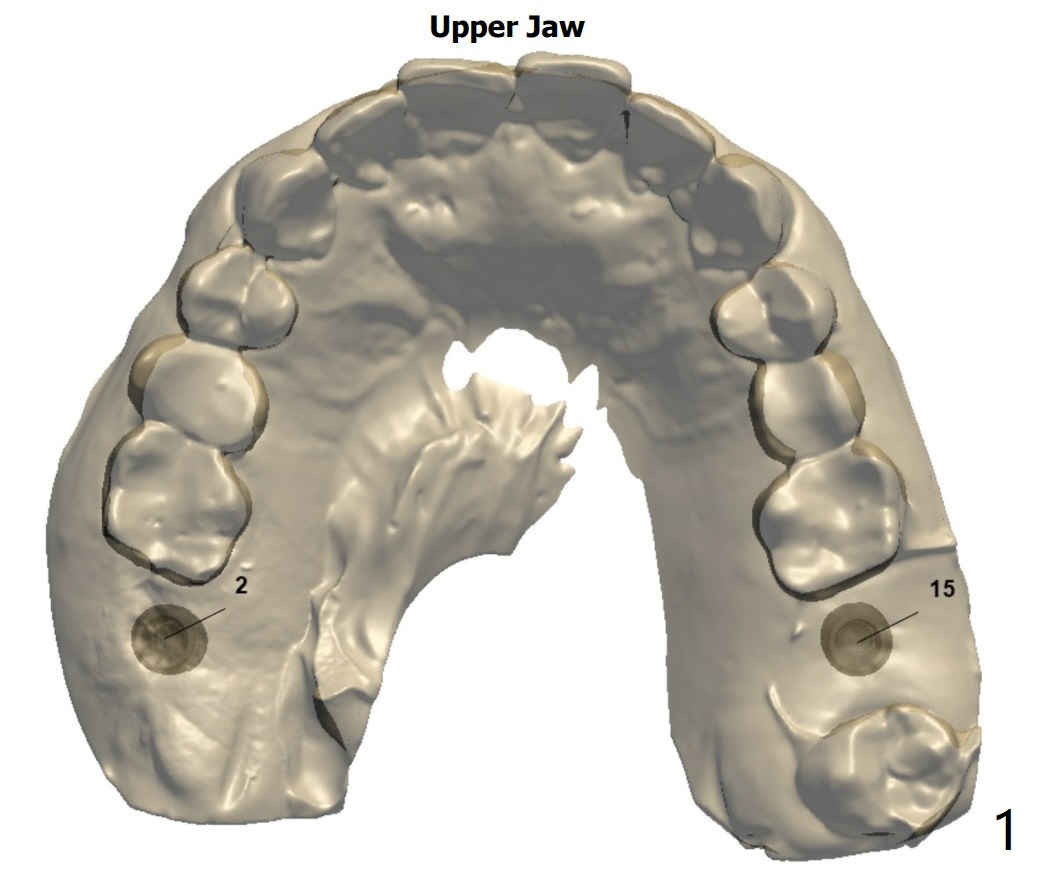

提升目的

Return to No Deviation  位点保留后

Xin Wei, DDS, PhD, MS 1st edition 10/09/2020, last revision 10/26/2020